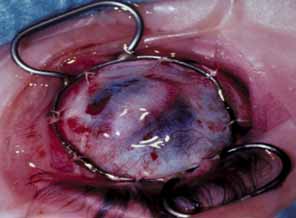

All patients with MPS and mucolipidoses in which corneal histopathology has been studied have demonstrated abnormal deposition of storage substrate, even in cases in which they were not clinically evident (Table 4). The hallmark histopathologic findings in these disorders are storage of excess glycosaminoglycan and glycolipid as membrane-bound vacuoles in keratocytes (Fig. 12). The glycosaminoglycans stain blue with colloidal iron and Alcian blue, and the glycolipids are best seen in frozen sections of unfixed tissue. Transmission electron microscopy demonstrates single membrane-bound cytoplasmic vacuoles containing fine fibrillogranular material along with lamellar bodies, likely representing glycosaminoglycans and glycolipids, respectively. These vacuoles can distend the keratocyte to many times their normal size, making them clinically visible as fine punctuate opacities. In more advanced cases, a fine extracellular granular material surrounds the keratocyte and contributes to the gray stromal haze seen clinically.

Fig. 12 Cornea showing subepithelial accumulation of glycosaminoglycan (colloidal iron, ×400). B. Cornea from MPS-VI micrograph shows fibrillogranular material in the cytoplasm of keratocytes (×6000). (courtesy of K. Kenyon, MD)

There are also disorders for which the corneal opacity is not a result of keratocyte involvement.90 In Fabry's disease, although there is some keratocyte involvement, it is postulated that the corneal opacity results primarily from sphingolipid deposition in the epithelial cell layer.94 In mucolipidosis IV, a majority of lipid deposition also occurs in the epithelial layer with relative sparing of the keratocytes.90 In cases with epithelial involvement, the epithelial cells become distended and disrupted like the keratocytes, and in more advanced cases fibrous proliferation occurs at the level of Bowman's layer.